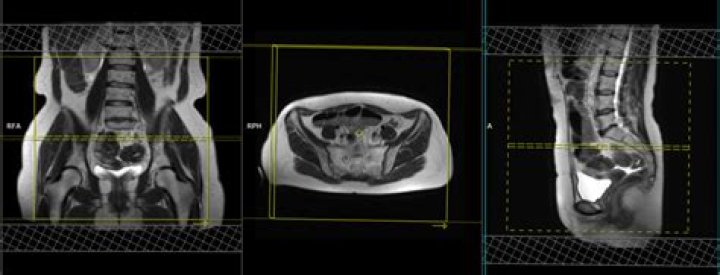

Can you see endometriosis on pelvic MRI?

Pelvic magnetic resonance imaging (MRI) is one imaging technique that doctors may use to help diagnose endometriosis. The test provides a picture of organs inside the pelvic cavity and shows endometrial growths that may require further investigation.

MRI is particularly helpful in ultrasonographically-indeterminate pelvic masses and diagnosing endometriosis of the ureters, bladder, and rectosigmoid. Imaging is inadequate for detection of pelvic adhesions or superficial peritoneal implants.

On MRI, endometriomas present as solitary or multiple masses with a homogeneous hyperintense signal intensity on T1- and T1-fatsat sequences. The T1-fatsat helps differentiate endometriomas from mature cystic teratomas, which usually contain fat.

Currently, MRI is considered the best imaging technique for mapping endometriosis, since it provides a more reliable map of deep infiltrating endometriosis than physical examination and transvaginal ultrasound (TVUS) [8].

A pelvic MRI is the best imaging technique for preoperative staging of endometriosis. Compared with an ultrasound, it provides a more reliable picture of deep, infiltrating lesions that require further investigation.